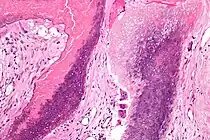

| Histopathology of pilomatricoma, high magnification, H&E stain, showing the characteristic components of basaloid cells and ghost cells. | |

The characteristic components of a pilomatricoma include a stroma of fibrovascular connective tissue surrounding irregularly shaped, lobulated islands containing basaloid cells (being darkly stained, round or elongated, with indistinct cell borders and minimal cytoplasm, with nuclei being round to ovoid, deeply basophilic and generally prominent nucleoli), which abruptly or gradually transitions into ghost cells (having abundant, pale, eosinophilic cytoplasm, well defined cell borders and a central clear area, but only faint traces of nuclear material), which in turn may transition into keratinaceous to amorphous necrosis.[11]

The presence of calcifications with foreign-body giant cells is common within the tumors.[12]